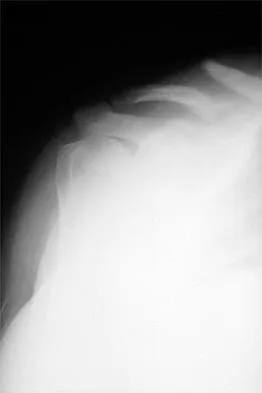

Question 32

A 12-year-old boy has severe left shoulder pain after being struck by an automobile. A chest radiograph, AP and lateral radiographs, and a CT scan with three-dimensional reconstruction of the scapula are shown in Figures 38a through 38d. Management should consist of

Explanation